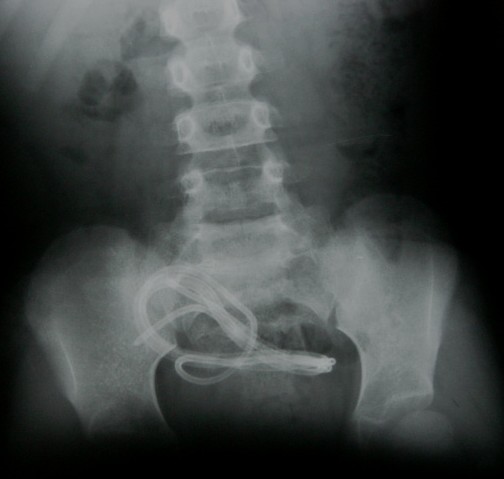

Migrasyon şant kateterinin bağlantı yerinden ayrılması ya da herhangi bir yerinde kopma veya kırılma sonucu yer değiştirmesidir. Sıklıkla karın boşluğuna giden peritoneal kateter kopma veya ayrılma sonucu karın boşluğu içine göç eder. (Resim 7). Yanlış yerleştirme, şant ameliyatından sonra grafi çekilmesi ile belirlenir.

Resim 7: Karın röntgen filminde peritoneal kateterin karın boşluğuna göç etmesi (migrasyon) görülmekte.